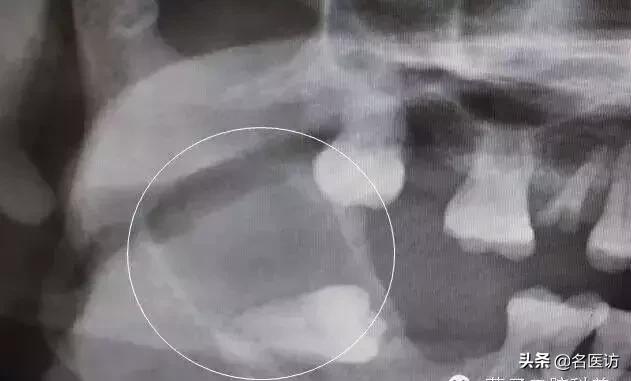

智齿引起下颌骨大面积囊肿